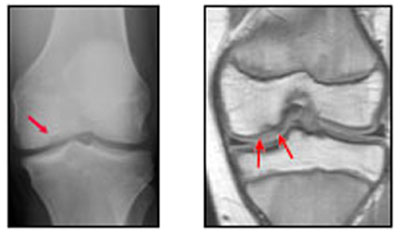

Osteochondritis Dissecans is a condition in which the area of bone just under the Cartilage surface is injured, leading to damage to the blood vessels of the bone. Without blood flow, the area of damaged bone actually dies. This area of dead bone can be seen on an X-ray and is sometimes referred to as the Osteochondritis lesion.

The lesions usually occur in the part of the Joint that holds most of the body's weight. It is more common for the lesions to occur on the medial Femoral Condyle, because this is the part of the Knee which bears more weight. This area is under constant stress and doesn't get time to heal.

Investigations: